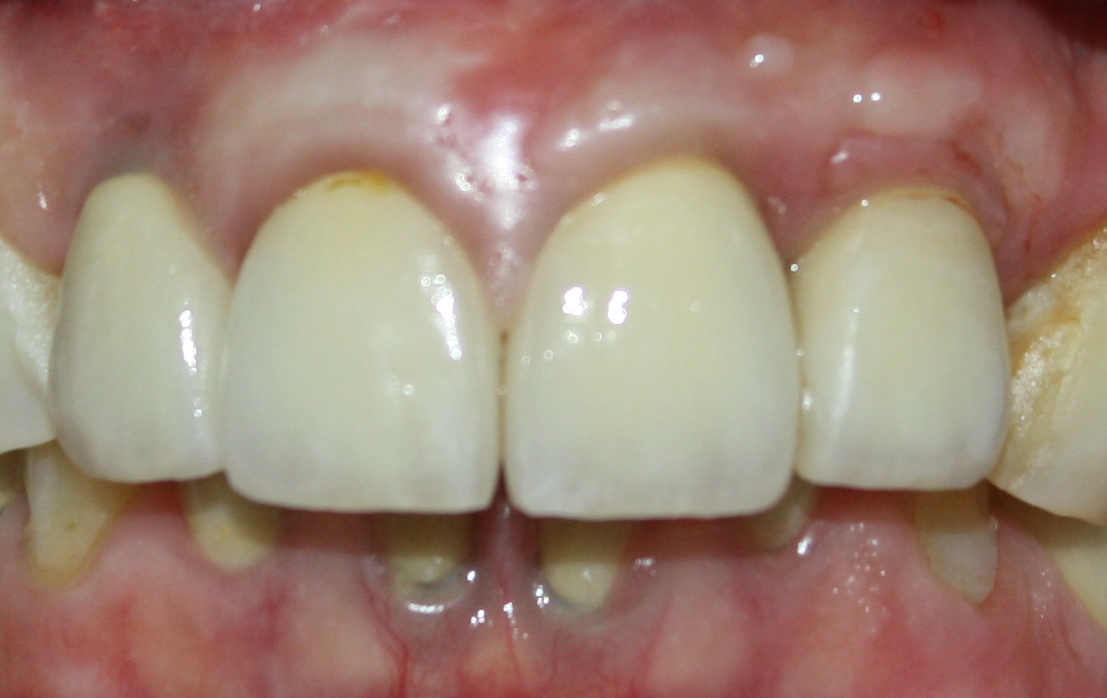

Около трёх лет назад к нам в клинику обратилась пациентка Мария, на момент обращения ей было 45 лет. Её беспокоила ситуация с передними резцами:

В ходе беседы она рассказала, что лечит эти зубы всю сознательную жизнь — их депульпировали («удалили нерв») из-за последствий травмы еще в школьном возрасте, и после этого каждые несколько лет (а то и чаще) ей приходилось перелечивать каналы, менять коронки, вкладки и т. д.

В результате, зубы приобрели очень уж нездоровый вид (см. фото выше). Вдобавок, всё усугубилось существенным снижением качества жизни — коронки и вкладки из зубов постоянно выпадают, десна вокруг них кровоточит при чистке…. Кроме того, Марию не покидает ощущение того, что эти зубы могут просто вывалиться в самый неподходящий момент. Именно это заставило её обратиться в нашу клинику.